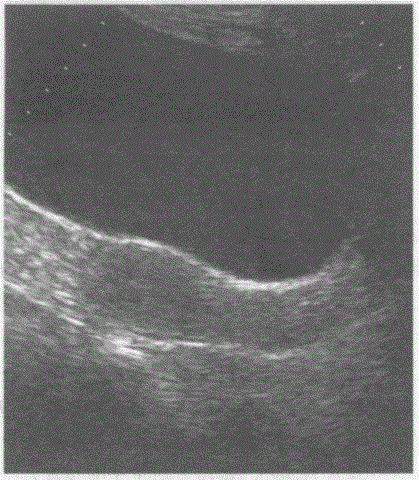

问题 临床资料:女,60岁,绝经6年,常规体检。 超声综合描述:子宫前位,测值减小,肌层回声均匀,宫内膜显示不清。 超声提示:

选项 A.绝经后子宫 B.子宫萎缩 C.正常子宫 D.A+B

答案 D